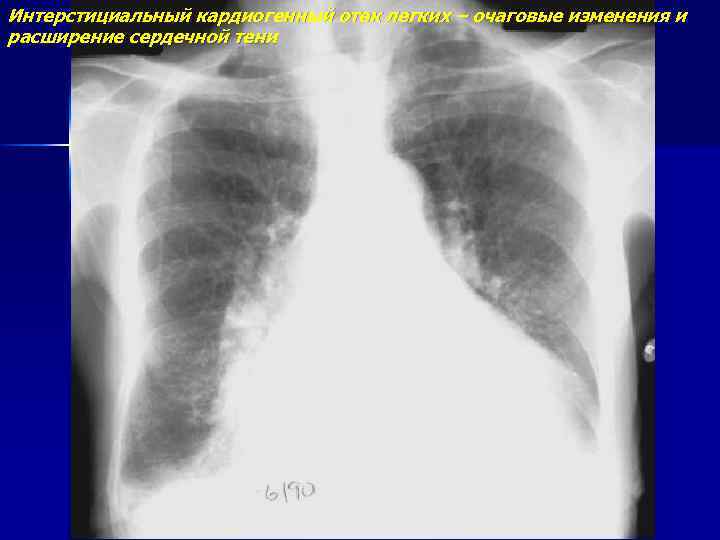

Интерстициальный кардиогенный отек легких – очаговые изменения и расширение сердечной тени